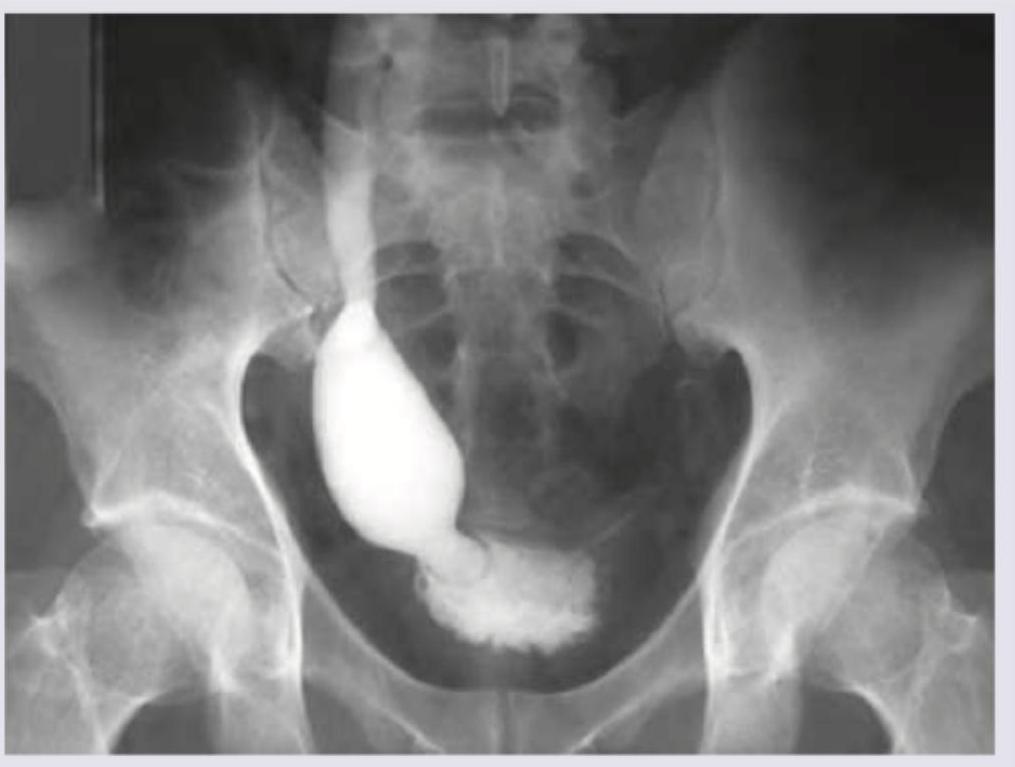

During evaluation of a child with recurrent UTI, VCUG is performed and the following finding is observed. What is the diagnosis?

Explanation: ***Posterior urethral valves*** - The image shows a **dilated and elongated posterior urethra** which is characteristic of posterior urethral valves (PUV). Also evident is **trabeculation of the bladder wall** and significant **bilateral vesicoureteral reflux (VUR)**, with a dilated and tortuous left ureter. - PUV frequently cause **recurrent UTIs** in male infants and children due to urinary obstruction and stasis, leading to bladder and upper tract damage. *Ureterocele* - A ureterocele would appear as a **cystic dilation of the distal ureter** into the bladder, typically visualized as a lucent defect within the opaque bladder on VCUG. The image does not show this specific finding. - While it can cause obstruction and VUR, the obstruction pattern observed in the image (especially the posterior urethra) is not consistent with a ureterocele. *Ectopic ureter* - An ectopic ureter involves the ureter inserting into an abnormal location, such as the vagina, urethra, or seminal vesicle, often bypassing the bladder. This would lead to a more direct drainage outside the bladder or into another structure without the gross changes seen in the posterior urethra. - While an ectopic ureter can lead to reflux or obstruction affecting the kidney, the primary obstruction in the **posterior urethra** with characteristic valve morphology is absent with an ectopic ureter. *Hydronephrosis* - **Hydronephrosis** refers to the swelling of a kidney due to a backup of urine, often caused by an obstruction or VUR. While hydronephrosis is a *consequence* of conditions like PUV, it is not the *diagnosis* explaining the direct VCUG findings in the bladder and urethra. - The VCUG directly visualizes the obstruction in the posterior urethra and associated reflux/bladder changes, which are the primary diagnostic features, rather than just the renal swelling.